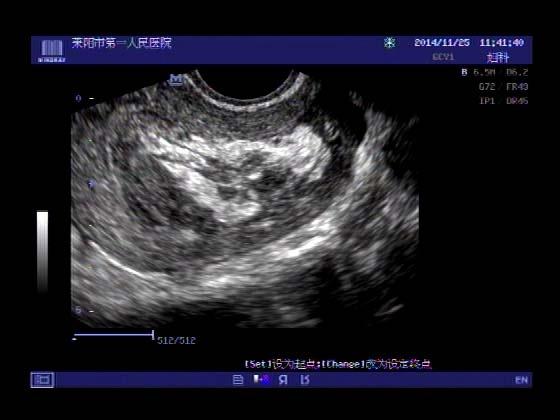

超声入门贴379---------粘膜下肌瘤(阴超的魅力)

女,43岁,月经量多3个多月,加重一个月

外院彩超检查提示:子宫后肌壁略高回声团------肌瘤?息肉?,盆腔少量积液

今天来我院检查:

巧妇难为无米之炊,经腹部超声确实很难定,阴超一目了然,乡镇医院诊断水平的提高更迫切的需要高档仪器的引进!